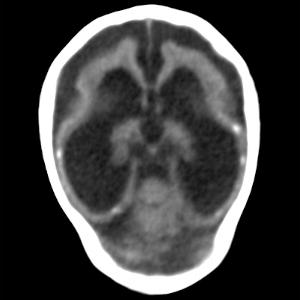

Figure 4. Images obtained in the case of an 18-year-old woman, first seen for rash at 10 weeks of pregnancy, with confirmed Zika virus infection. US findings obtained at 20 weeks of gestational age were reportedly normal, with normal head circumference of 17.5 cm. At 37 weeks of gestational age, (a) sagittal transvaginal and (b) coronal transabdominal US images obtained with the head upside down show a small head circumference (26.4 cm, corresponding to 28 weeks 5 days, below the 3rd percentile), moderate ventriculomegaly with dense intracranial calcifications (arrowheads on a), and abnormal head shape with flattened appearance and thickened skin (arrow on a). On the sonogram, it is difficult to precisely localize the calcifications, given the thin parenchyma. (c, d) Axial bone window CT images, (e) sagittal localizer CT image, and (f–h) axial CT images show microcephaly with cerebral atrophy, and, despite ventriculomegaly, the extra-axial cerebrospinal fluid spaces are still prominent. The hypoattenuating calcifications are predominantly located in the subcortical white matter at the gray matter–white matter interface. There is markedly abnormal skull shape with some eversion of the bones at the suture sites (particularly frontoparietal sites), with redundant skin folds (particularly in the parieto-occipital region). (i) Sagittal T1-weighted, (j, k) coronal T2-weighted, and (l) axial susceptibility-weighted MR images obtained at 1 month of age show an undersegmented midbrain, severe microcephaly, open sylvian fissures, and polymicrogyria. The dense calcifications are evident on the susceptibility-weighted image. On the sagittal images (a, e, i), note the small supratentorial compartment and associated skull deformity.